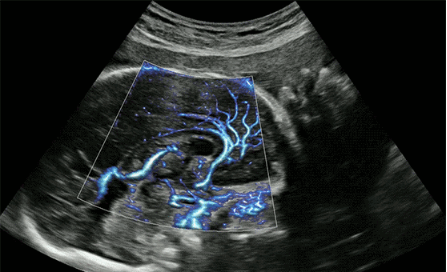

CrystalLive?是三星最新的超聲成像引擎,同時(shí)增強(qiáng)了2D圖像處理能力、3D渲染能力和彩色信號(hào)處理能力,能夠在復(fù)雜情況下提供出色的圖像性能,具備檢測(cè)外周血管、微循環(huán)血流的能力。